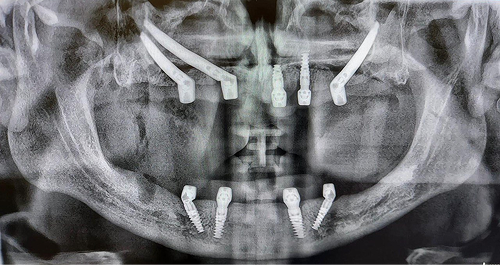

Klasyczny protokół ZYGOMA

Przeznaczony dla pacjentów z brakiem dostatecznej ilości kości szczęk w zakresie całego górnego łuku. Protokół implantoprotetyczny zakłada wprowadzenie podczas procedury 4 implantów Zygoma.

Protokół QUAD ZYGOMA

Przeznaczony dla pacjentów z brakiem dostatecznej ilości kości w zakresie całego górnego łuku. Rozwiązanie zakłada 4 implanty jarzmowe, 4 łączniki MultiUnit, natychmiastowy tymczasowy most wykonany z akrylu, o ile jest to możliwe.

MOŻLIWE INNE ROZWIĄZANIA

Indywidualne podejście do każdego pacjenta jest kluczowe. O ilości wszczepionych implantów jarzmowych Zygoma decydują warunki kostne szczęki u danego pacjenta. W sytuacji braku wystarczającej ilości kości w odcinkach bocznych, czyli w okolicy zębów przedtrzonowych i trzonowych, oraz przy wystarczającej jej ilości w odcinku przednim podnosowym, wszczepia się pojedyncze implanty zygomatyczne – symetrycznie po obu stronach oraz 4 lub 2 tradycyjne, krótkie implanty zębowe w odcinku przednim. U pacjentów z brakiem wystarczającej ilości kości szczęk w odcinkach bocznych oraz przednim, by założyć tradycyjne, krótkie implanty, wprowadza się symetrycznie po dwa implanty jarzmowe Zygoma po każdej ze stron. U pacjentów bezzębnych, u których zanik kości jest znaczny, wszczepienie implantów wymaga precyzyjnego planowania. Ilość i rozmieszczenie implantów jarzmowych jest dostosowywana do anatomii pacjenta. Pomocne bywają również tzw. implanty skrzydłowe, które po wprowadzeniu stabilizowane są w wyrostkach skrzydłowych kości klinowych, które zrastają się z tylnymi obszarami szczęk tzw. guzami szczęk. Są to implanty mocowane w jamie ustnej z tyłu, za typową pozycją implantu jarzmowego. Dodatkowo o możliwości wprowadzenia implantów jarzmowych decydują warunki anatomiczne twarzoczaszki pacjenta, objętość kostna kości jarzmowej, zakres rozwierania szczęk, który stwarza lub ogranicza możliwość dotarcia do pola operacyjnego.